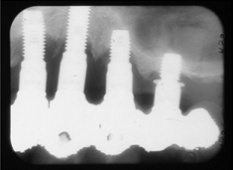

- 歯周病が進行しやすくなる可能性がある。